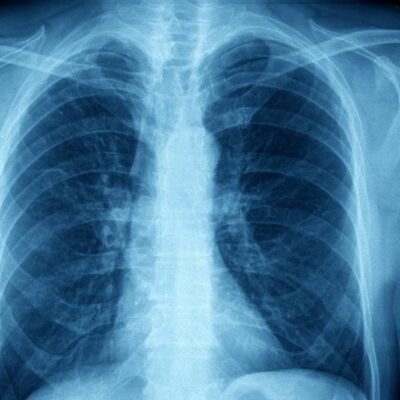

Possible Complications of Asthma

Asthma is a condition that affects an estimated 300 million people across the globe. There are a number of complications that can arise for asthma patients. Some of these include- Increased risk of infections such as pneumonia or influenza. Decreased quality of life due to poor management of the condition.